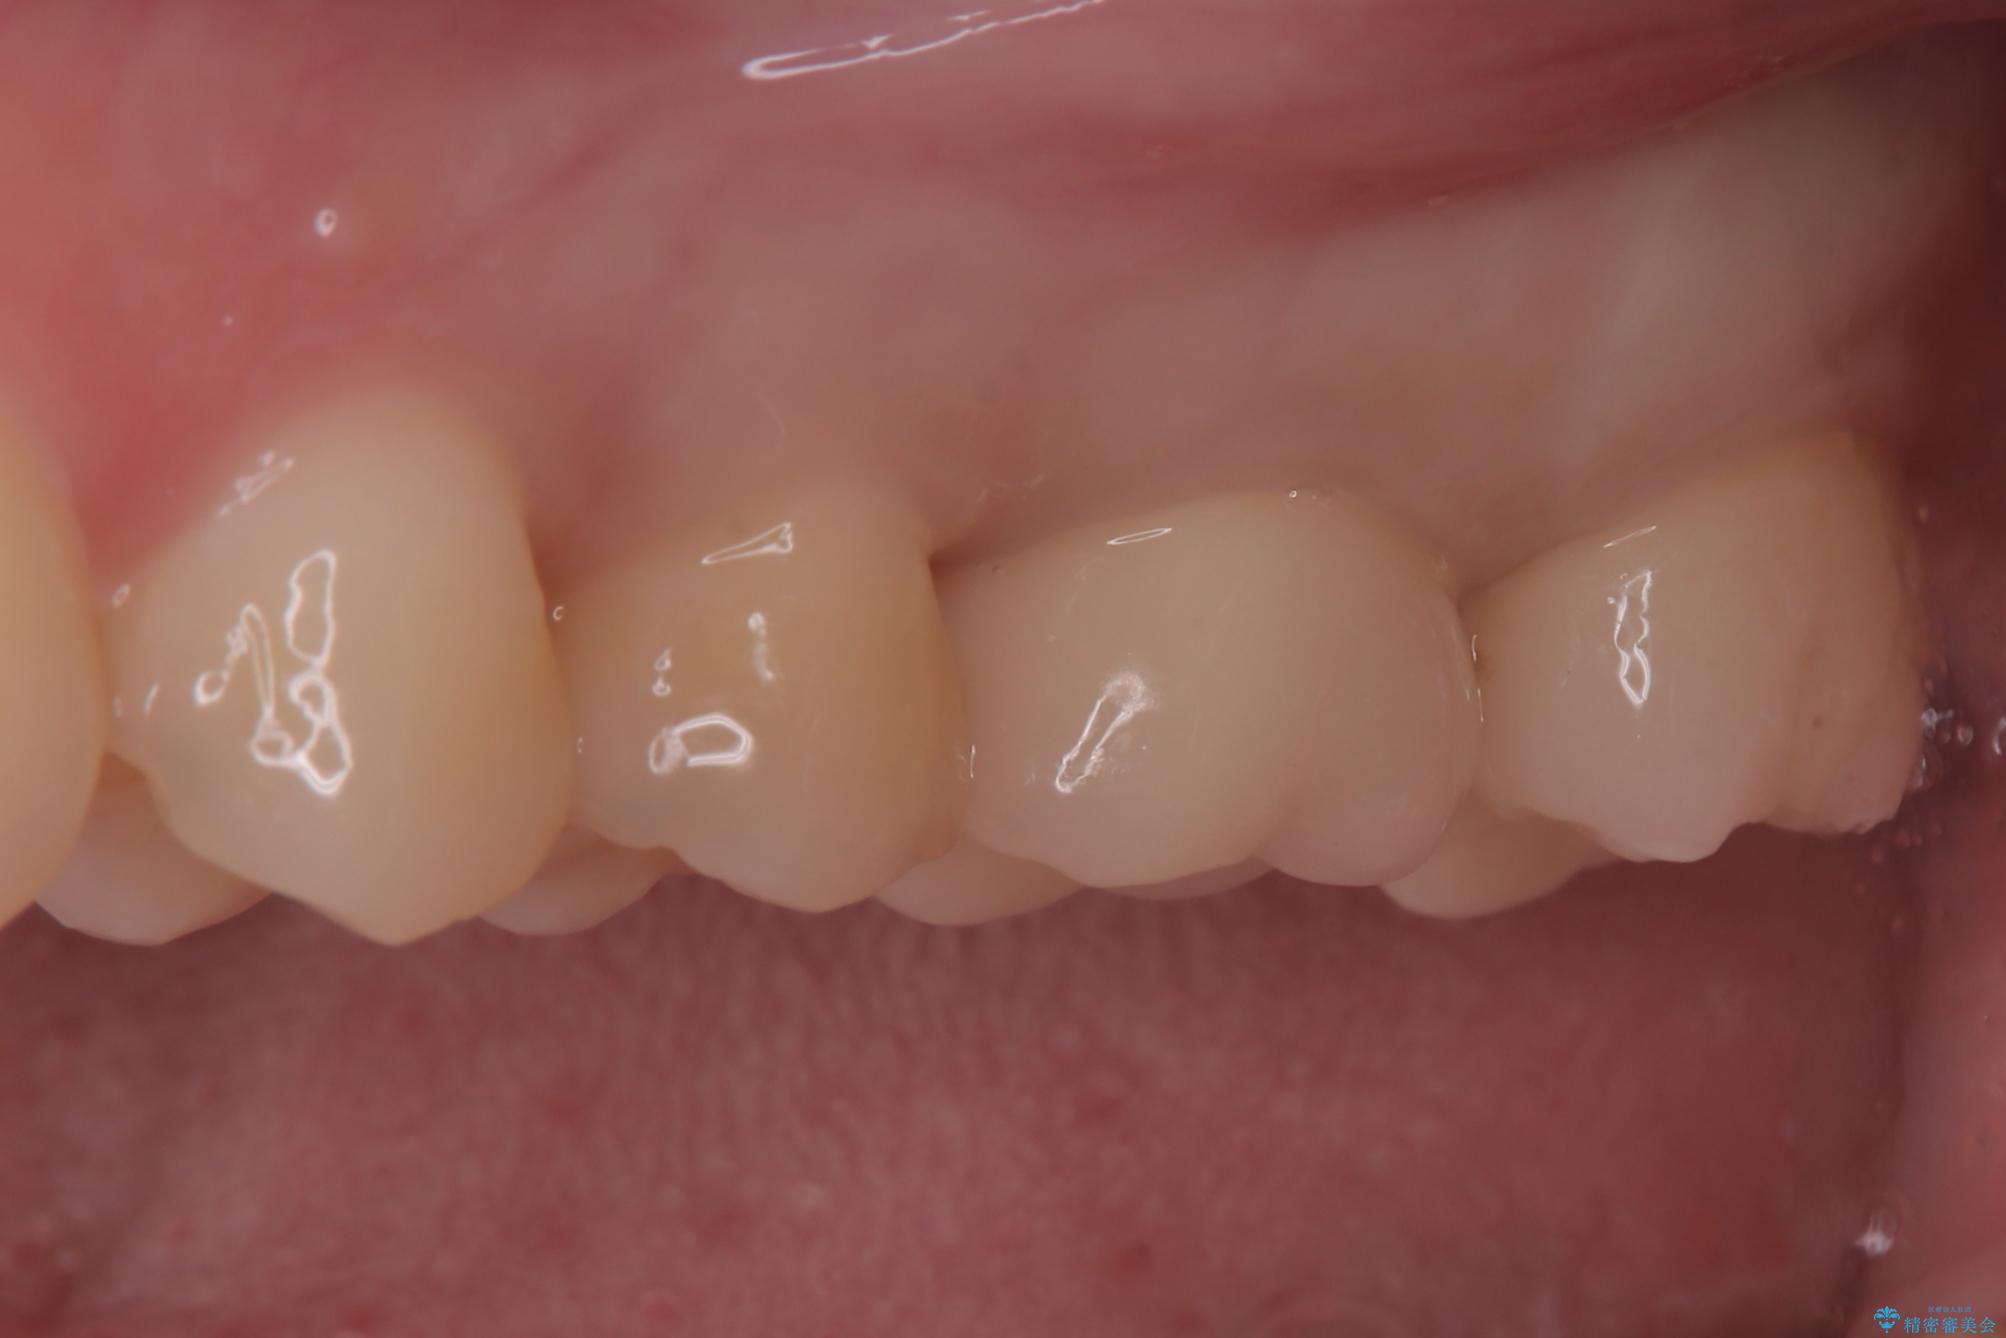

セラミックによる修復: 最終的な被せ物(または詰め物)にはセラミックを使用しました。高い適合性により、二次的な虫歯のリスクを抑えつつ、天然歯のような自然な咬み心地と美しさを再現しました。